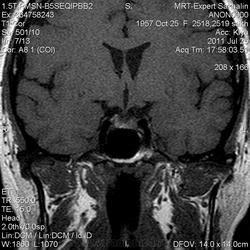

Как мы "динамичим"гипофиз

Женщина.6 лет назад выявлено образование левой доли нейрогипофиза.Пришла на контроль.

Постконтраст

Мне самой показался случай не совсем ясным, но динамик четко показывает участок с отставанием в контрастировании, воронка смещена вправо-о чем  думать бедному начинающему специалисту?

Кстати, немного о внимательности-номера протоколов могут многое подсказать!